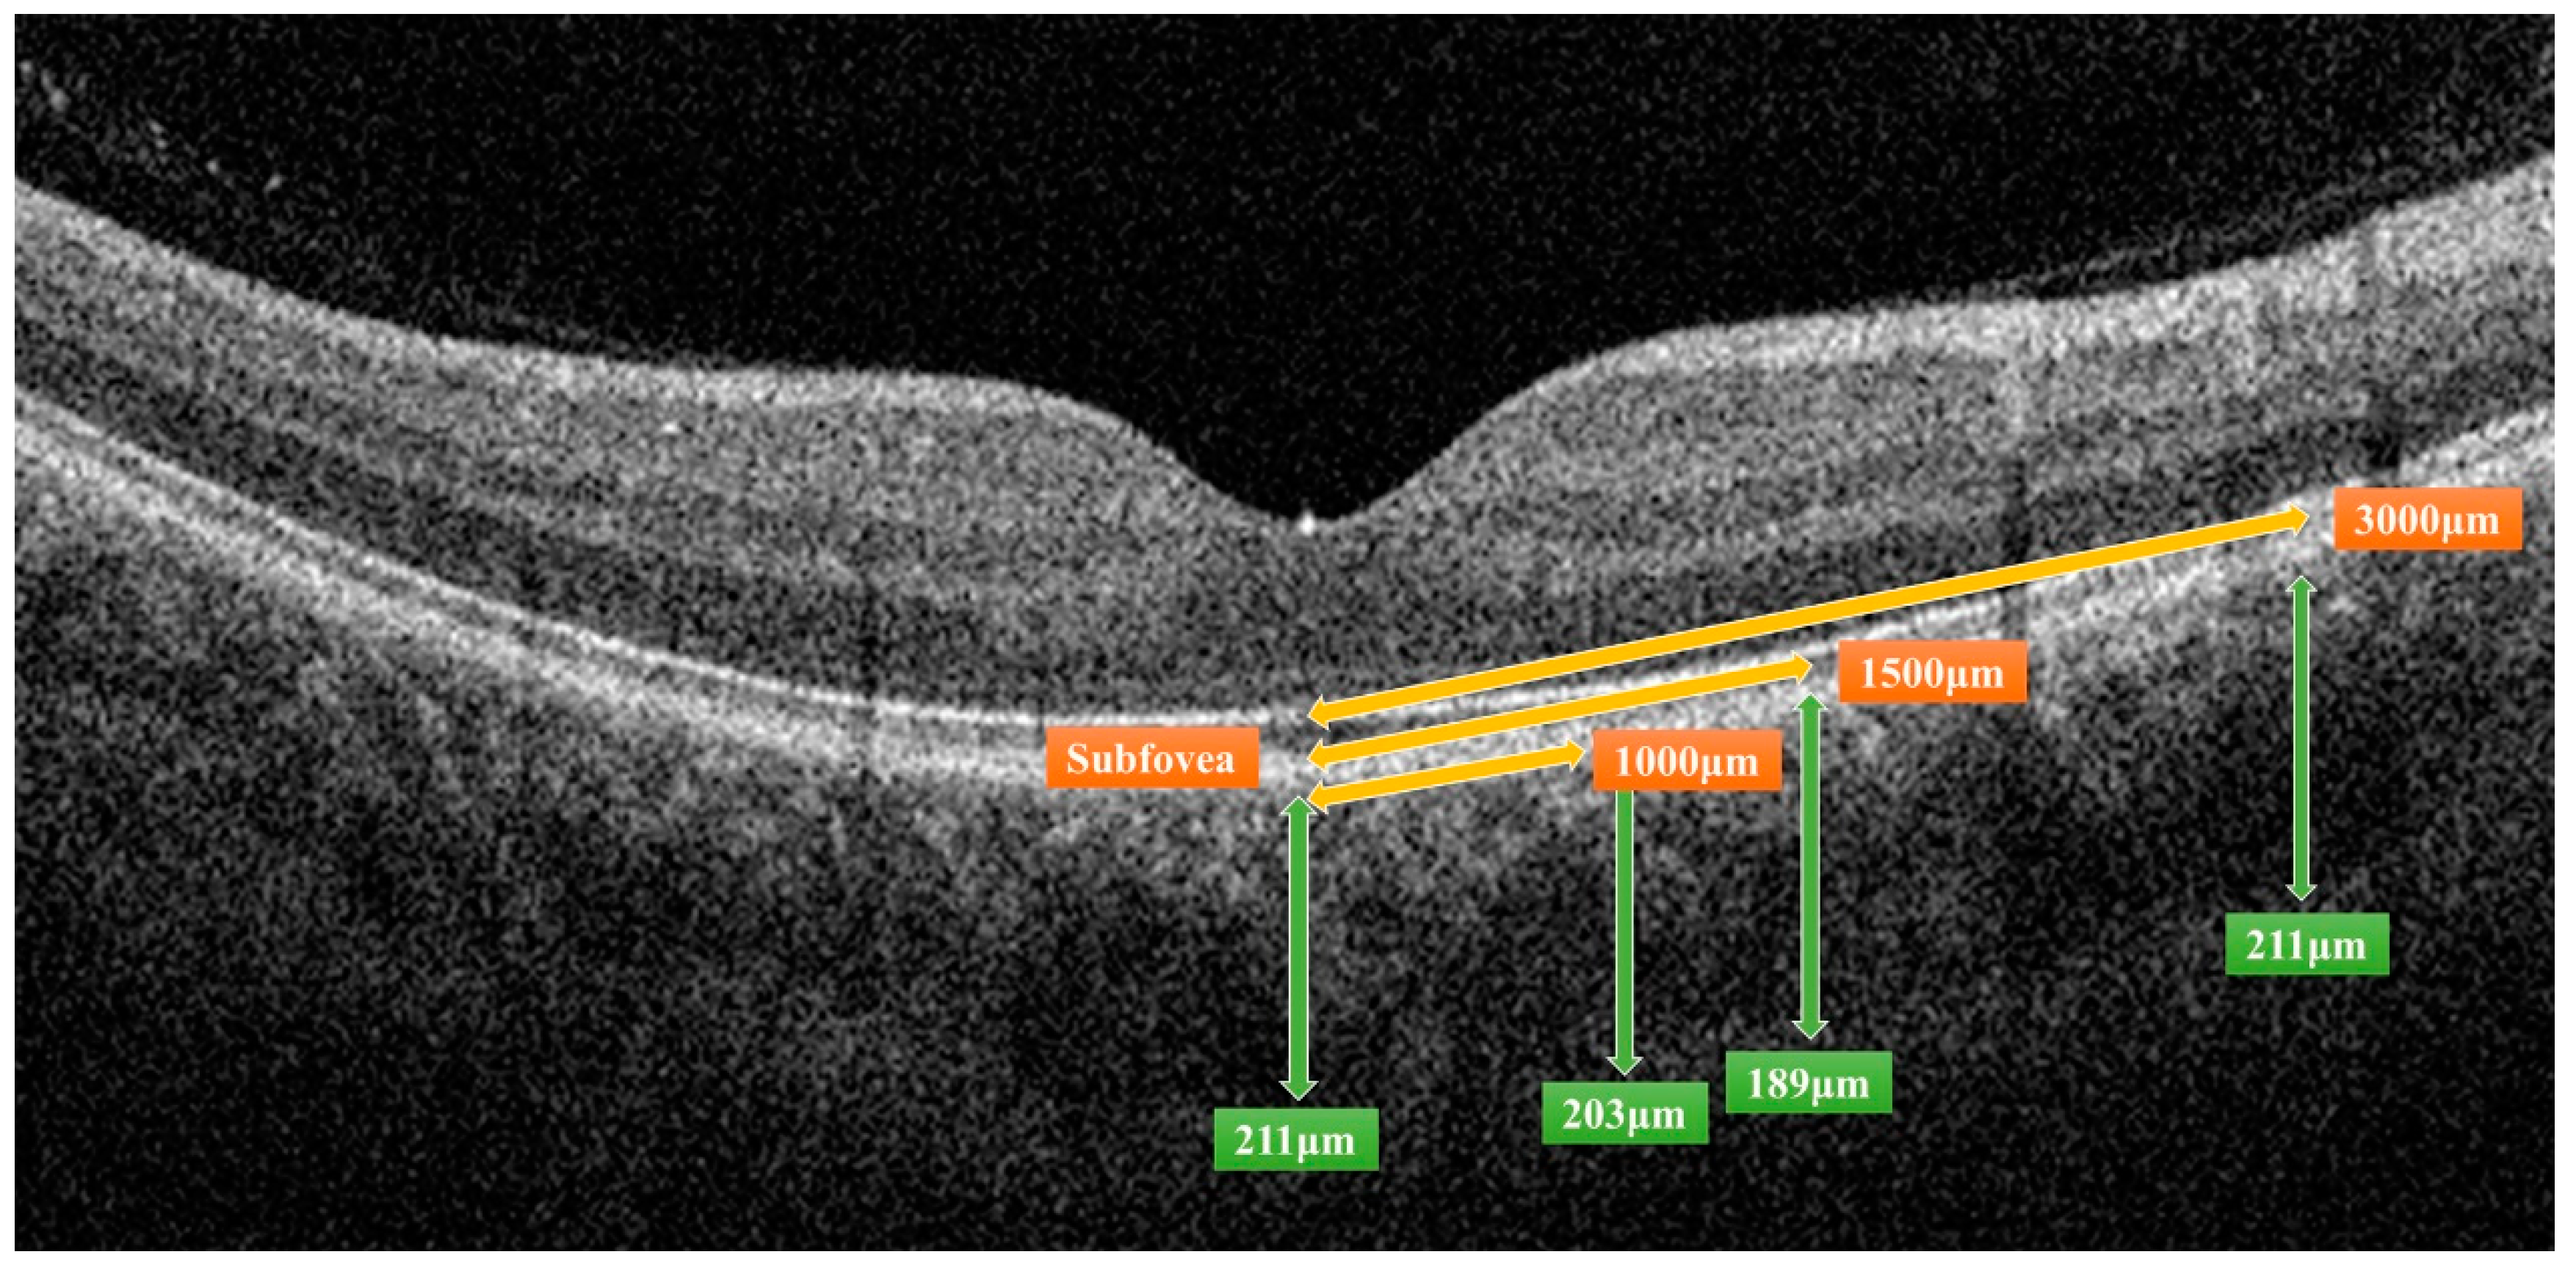

| Location of CTh | No DR n = 23 | Mild NPDR n = 21 | Moderate NPDR n = 15 | Severe NPDR n = 12 | PDR n = 8 |

|---|---|---|---|---|---|

| Subfoveal | 215.4 ± 95.2 | 234.1 ± 99.2 | 193.9 ± 70.5 | 253.9 ± 81.8 | 297.7 ± 81.0 |

| p-value | - | 0.406 | 0.406 | 0.052 | 0.076 |

| 1000 μm (average) | 199.0 ± 85.3 | 223.3 ± 94.8 | 180.0 ± 65.0 | 235.0 ± 71.1 | 260.0 ± 66.5 |

| p-value | - | 0.285 | 0.525 | 0.052 | 0.085 |

| 1500 μm (average) | 192.9 ± 78.5 | 209.7 ± 84.5 | 174.6 ± 61.0 | 226.3 ± 64.1 | 247.3 ± 65.9 |

| p-value | - | 0.428 | 0.489 | 0.050 | 0.085 |

| 3000 μm (average) | 169.7 ± 67.8 | 182.1 ± 60.5 | 160.2 ± 48.5 | 196.9 ± 46.4 | 235.0 ± 40.8 |

| p-value | - | 0.285 | 0.765 | 0.014 | 0.024 |